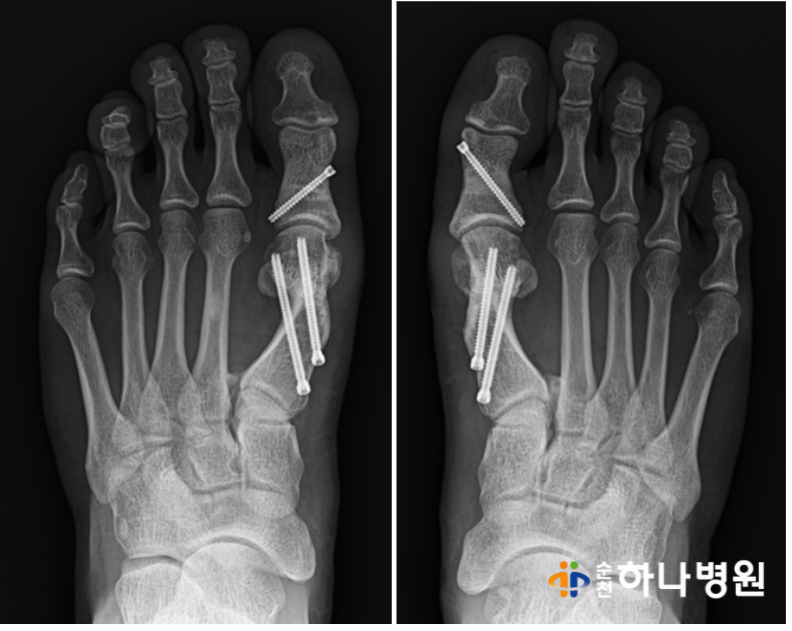

무지외반증 수술 후 각도 확인 결과

우측 ( 무지외반각도 31' / 제 1-2중족골간각도 16')

→ (무지외반각도 9' / 제1-2중족골간각도 7')

좌측 (무지외반각도 25' / 제1-2 중족골간각도 16')

→ (무지외반각도 9' / 제1-2 중족골간각도 8')

모두 중등도 변형에서 '정상'으로 회복된 모습을

확인할 수 있습니다.

사진에서도 보시다시피

양측 모두 엄지발가락 2번째 발가락을 밀지 않고

평행한 모습을 보실 수 있습니다^^

제1중족골두가 툭 뒤어 나와있던

부분 또한 없어진 모습!